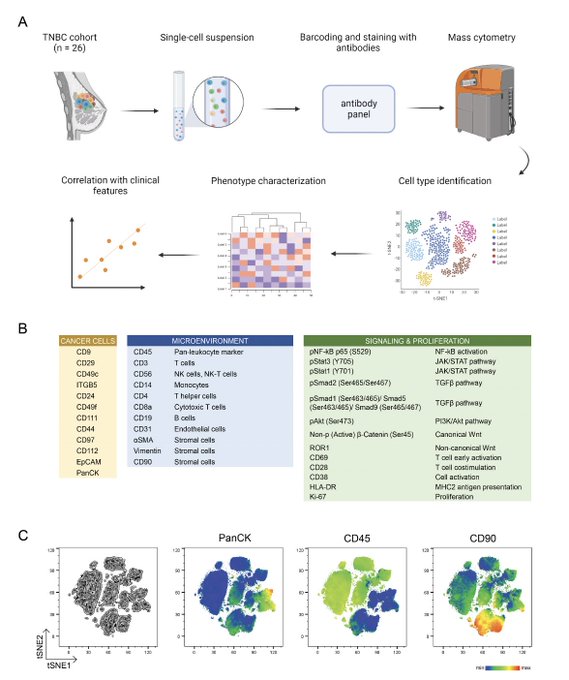

Single-cell protein profiling defines cell populations associated with triple-negative breast cancer aggressiveness.

Molecular Oncology.

2022,

ISSN: 1574-7891,

PMID: 36550781,